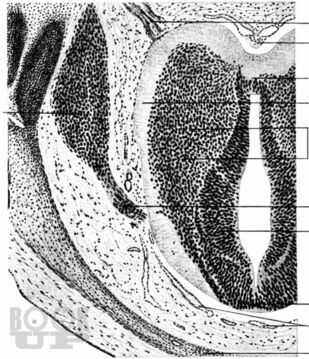

В пособии представлены современные данные о закономерностях эмбрионального и постнатального развития мозга человека, а также сведения о возрастных особенностях мозгового обеспечения психических функций. Приведены базовые сведения о морфогенезе мозга и его нарушениях, структурно-функциональных основах становления двигательных систем мозга и возрастной динамике развития двигательных навыков в онтогенезе, рассматриваются вопросы развития перцепции, внимания и речевых функций.